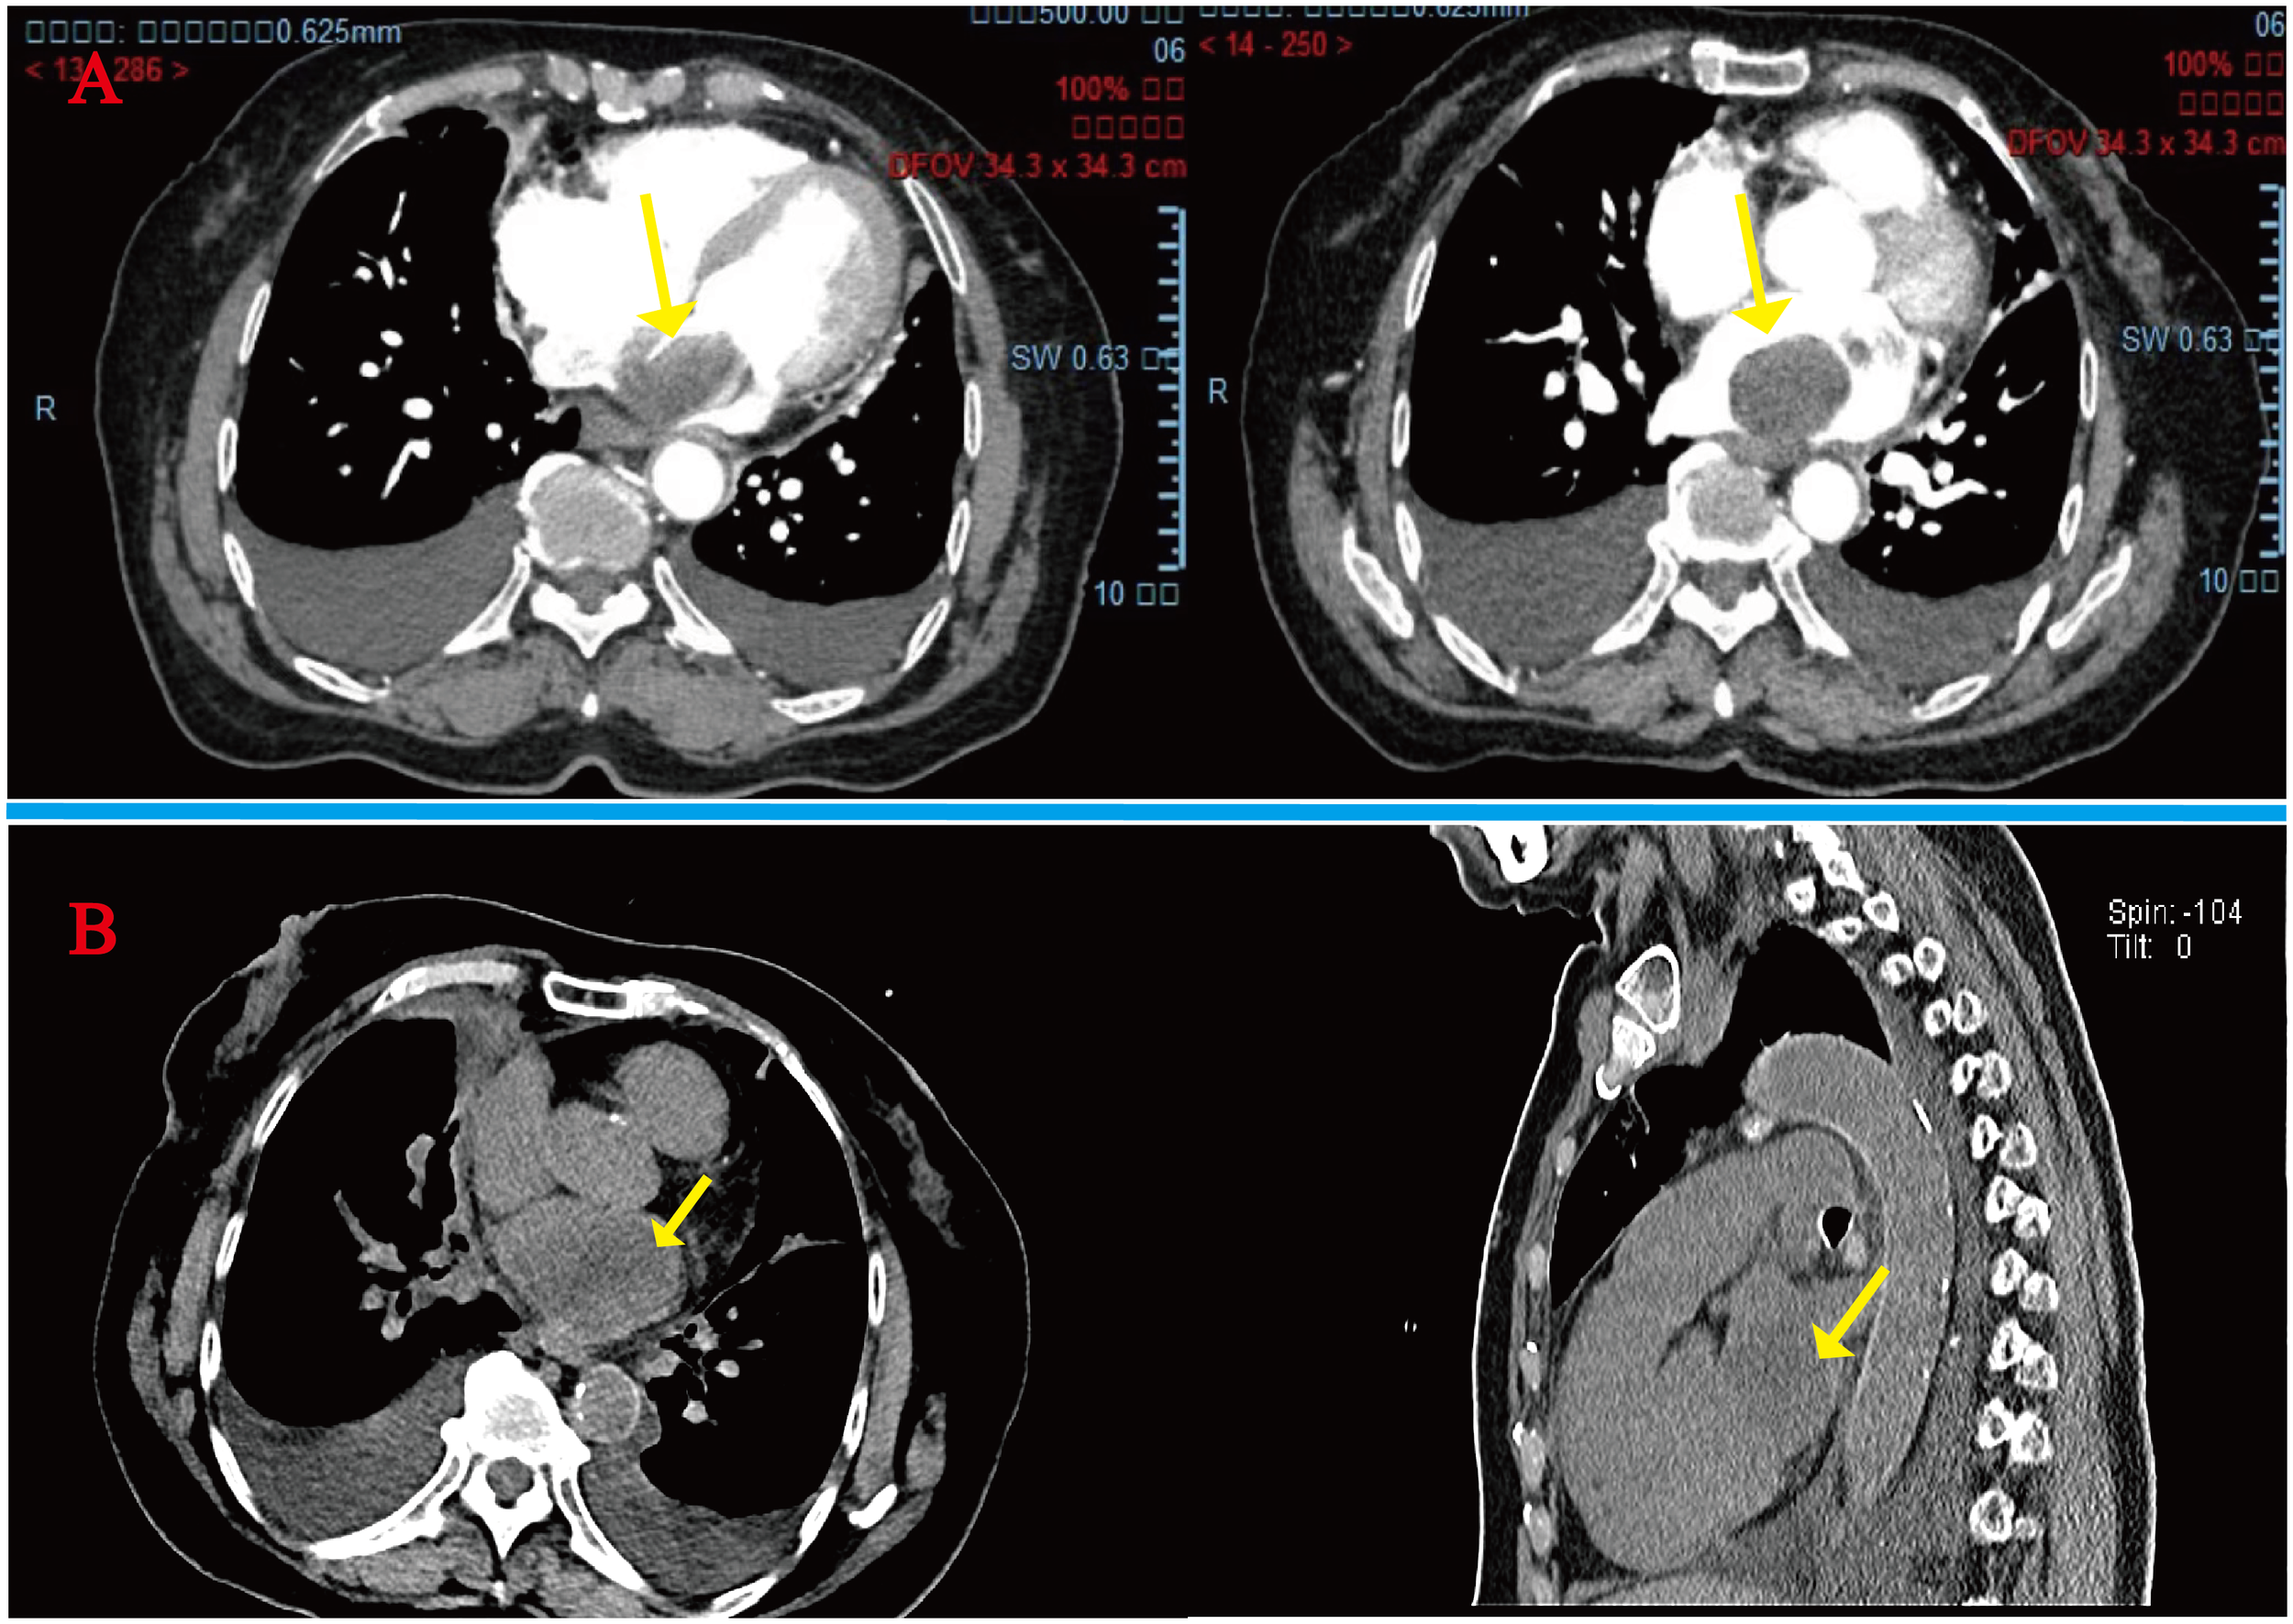

A 78-year-old woman presented to the outpatient clinic for “COVID-19” infection. Transthoracic echocardiography (TTE) revealed a left atrial hypoechoic mass measuring 85 mm × 55 mm × 35 mm. This mass was located in the left atrium and had a wide base connecting it to the left atrial wall. During diastole, part of the hypoechoic mass was visible, allowing blood flow to be expelled into the left ventricle through the mitral valve orifice. Additionally, mild mitral regurgitation was observed. Notably, TTE showed that the left ventricular ejection fraction (LVEF) was preserved at 68% (Figure 1), and the patient did not present any symptoms regarding the cardiovascular system. An enhanced computed tomography (CT) scan of the chest, abdomen, and coronary arteries on admission showed a filling defect in the left atrium, which was likewise considered to be atrial tethering (Figure 2). Cardiac CT and coronary angiography showed coronary atherosclerosis, including moderate stenosis of the left anterior descending branch in the middle part of the lumen and slight stenosis of the distal part of the right coronary artery. In addition, several suspicious lymph nodes were found in the mediastinum and adjacent to the great vessels. Laboratory tests revealed an N-terminal pro-B-type natriuretic peptide (NT-pro-BNP) level of 1030 pg/mL (normal range <450 pg/mL for those under 50 years old and <900 pg/mL for those over 50 years old) and a fibrinogen level of 4.88 g/L (normal range 2–4 g/L). The remainder of the admission tests did not indicate any abnormalities.

Figure 2

(A) Initial admission preoperative enhanced CT scan of the chest and abdomen: arrows indicate a homogeneous low-density mass almost entirely occupying the left atrium, extending into the left auricle and pulmonary artery opening. (B) Readmission CT tomography scan of the chest at 4 months postoperatively: tumor recurrence is seen at the arrows.

However, after the fourth month of surgery, she was readmitted to the hospital with severe heart failure symptoms, and a bedside TTE revealed a solid left atrial space causing mitral orifice obstruction, tricuspid regurgitation (moderate-to-severe), severe pulmonary hypertension, and a chest CT scan revealed a hypodense shadow in the left atrium and a large amount of pleural effusion. (Figure 2), We considered tumor recurrence and started urgent anti-heart failure therapy. The patient’s oxygen saturation level was extremely low, and we performed ventilator-assisted ventilation. However, on the second day after admission, the patient’s shortness of breath worsened, her consciousness appeared fuzzy, and she passed away after resuscitation (Figure 4).